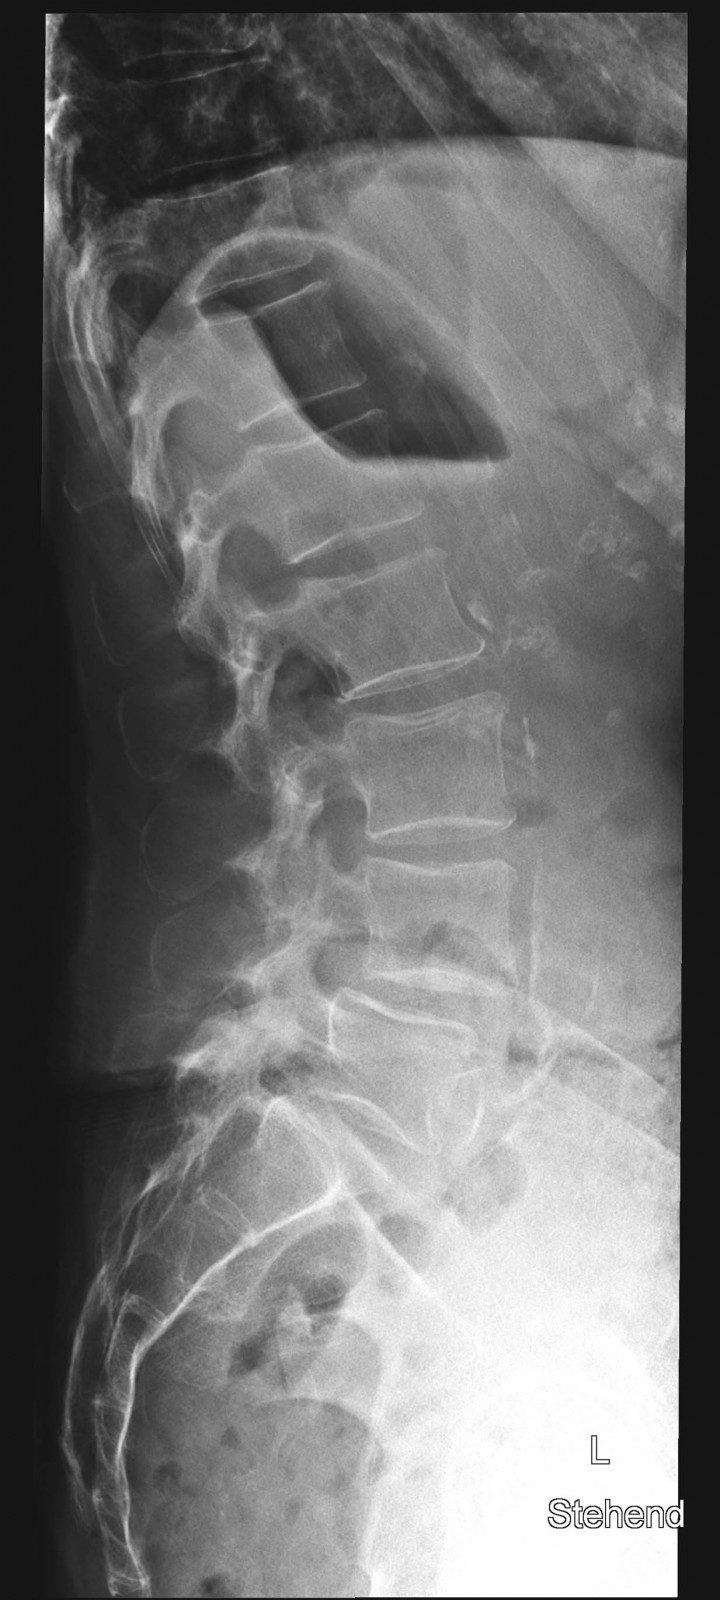

Röntgenfall des Monats März 2017 mit Auflösung

80 jährige Patientin mit chronischen linksbetonten Schmerzen lumbal am Übergang zum Becken